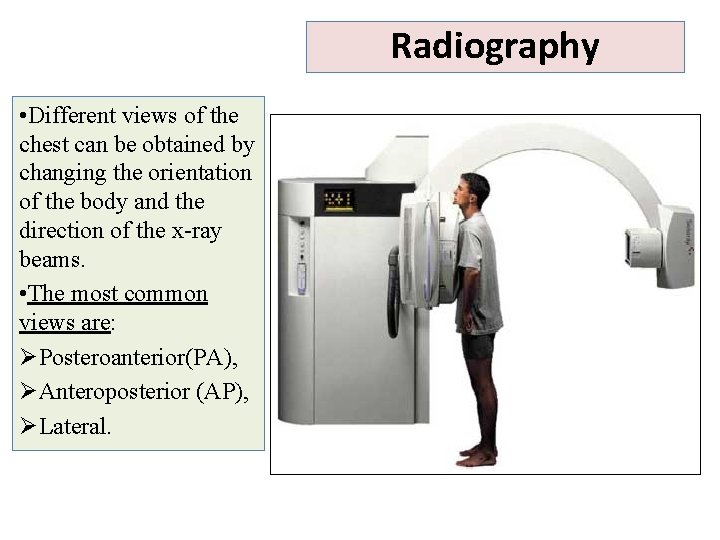

Radiography • Different views of the chest can be obtained by changing the orientation of the body and the direction of the x-ray beams. • The most common views are: ØPosteroanterior(PA), ØAnteroposterior (AP), ØLateral.